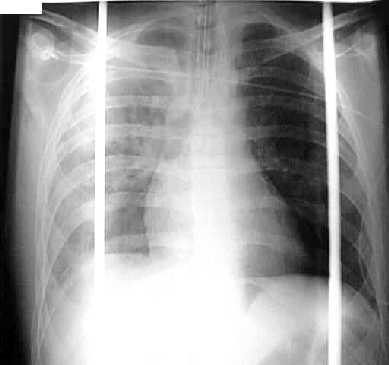

Un paciente varón de 43 años ingresa en Urgencias después de un accidente de tráfico, con fracturas de 3ª,4ª,5ª y 6ª costillas derechas y contusión pulmonar derecha.

Al 5 dia le aparece un sídrome de distrés respiratorio agudo del adulto y se inicia ventilación mecánica con PEEP

Dos dias mas tarde sufre un neumotórax izquierdo a consecuencia del barotrauma producido por la ventilación mecánica